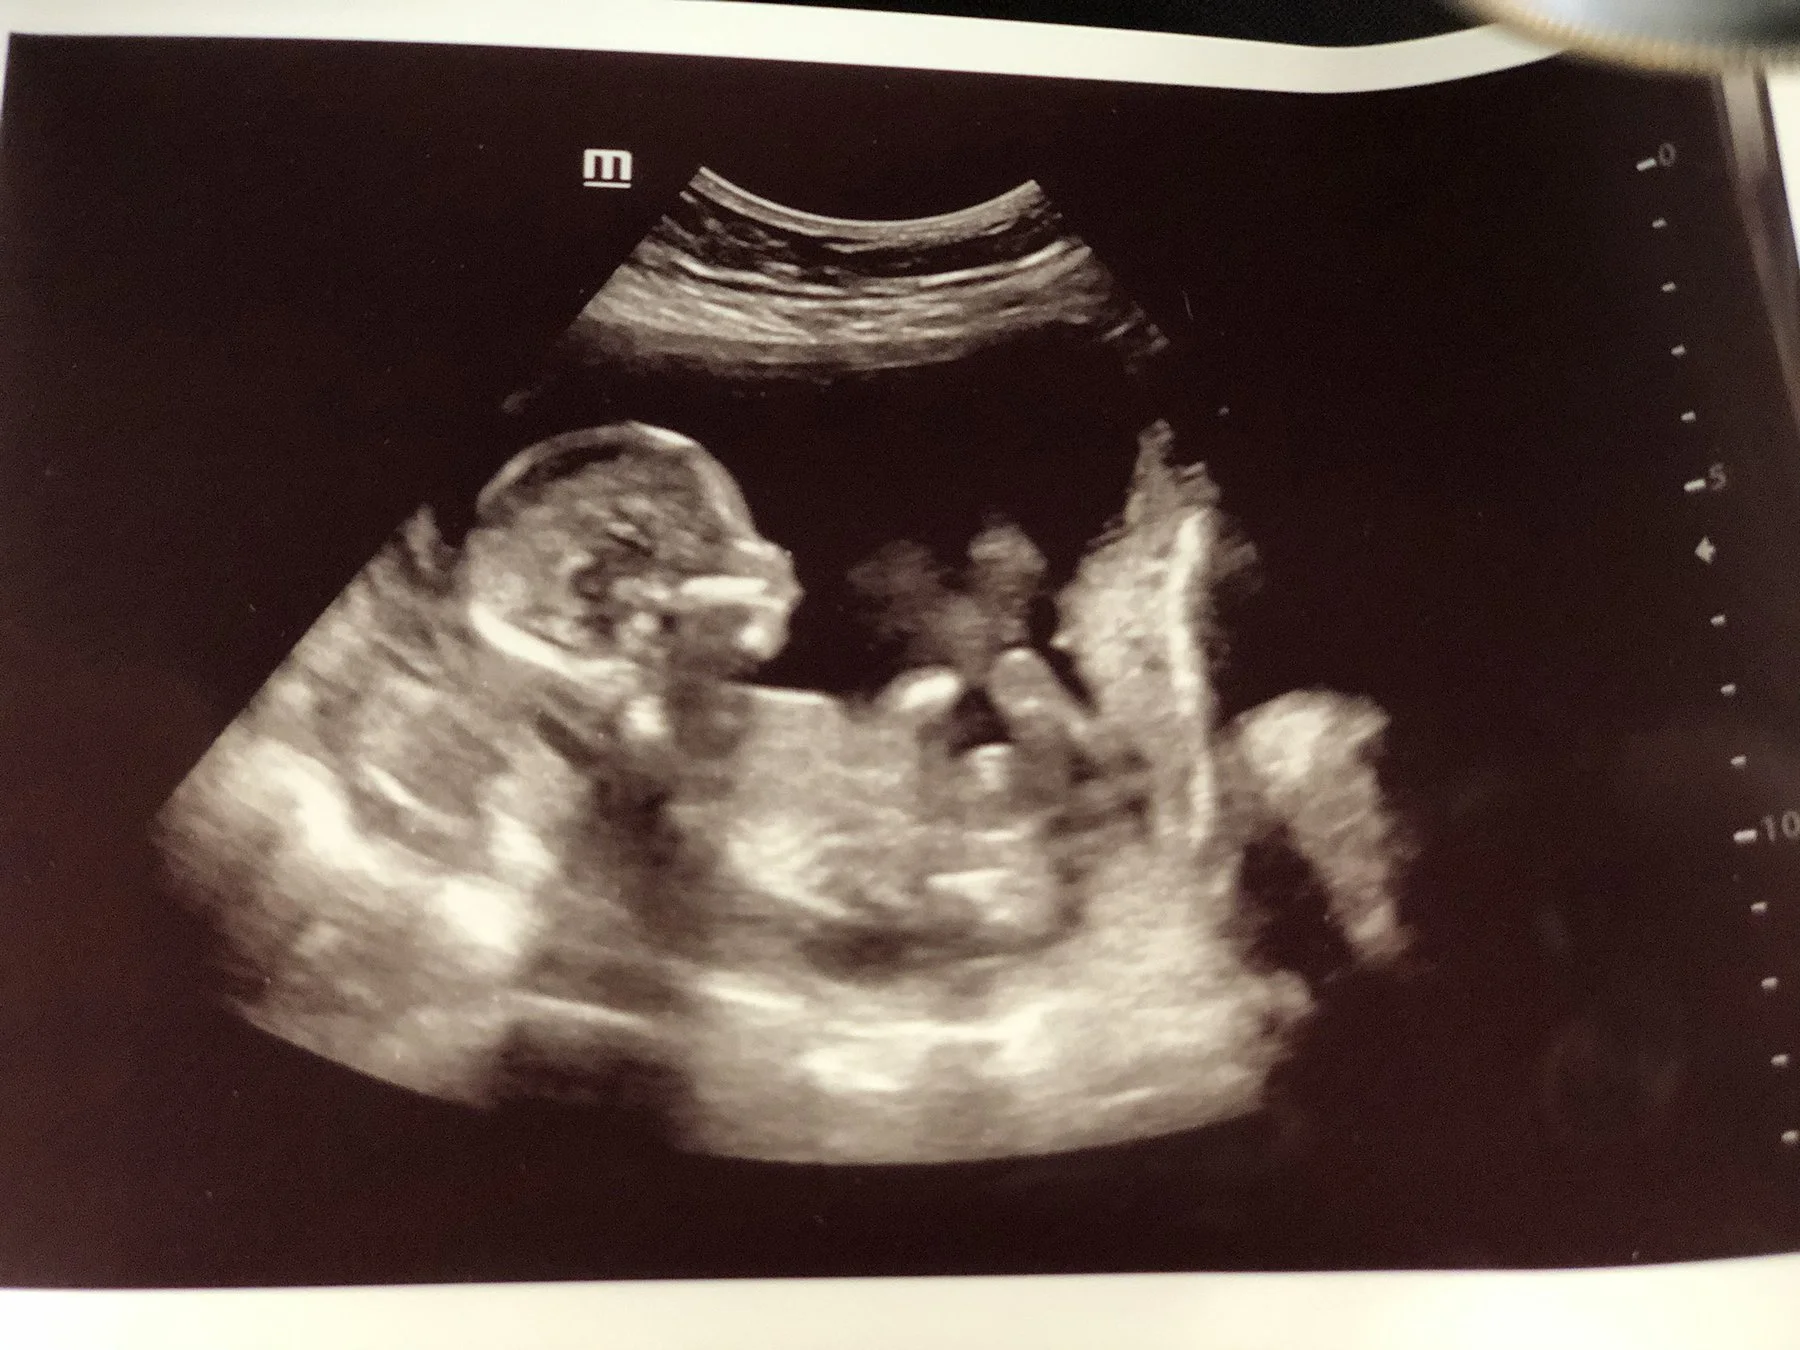

Inspired by a deeply personal ultrasound appointment—when we were asked if we wanted to abort our baby girl—this piece reflects on the weight of that moment and the life that could have been lost.

This poem is inspired by a personal ultrasound appointment—when we were asked if we wanted to abort our baby girl—this piece reflects on the weight of that moment and the life and joy that could have been lost.